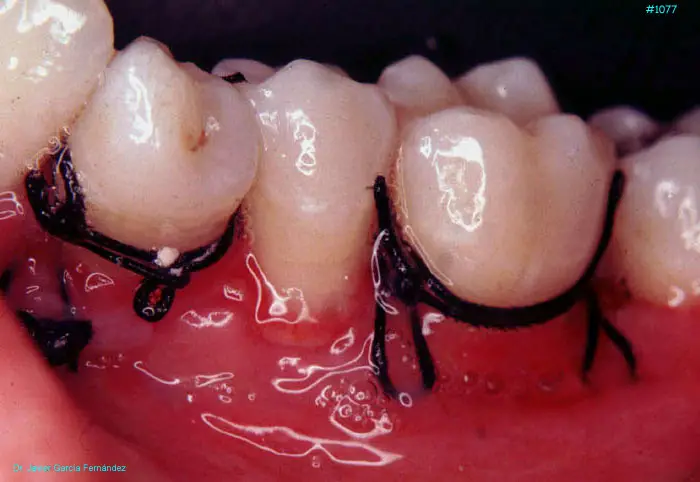

Atlas of Surgical Techniques in Periodontics. Chapter III. Atlas de Técnicas Quirúrgicas en Periodoncia